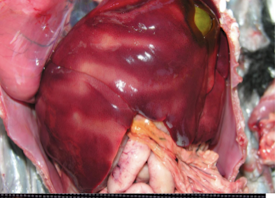

What is occuring in this image? Why?

• Tissues surrounding gallbladder will become stained yellow due to degradation of gall bladder wall.